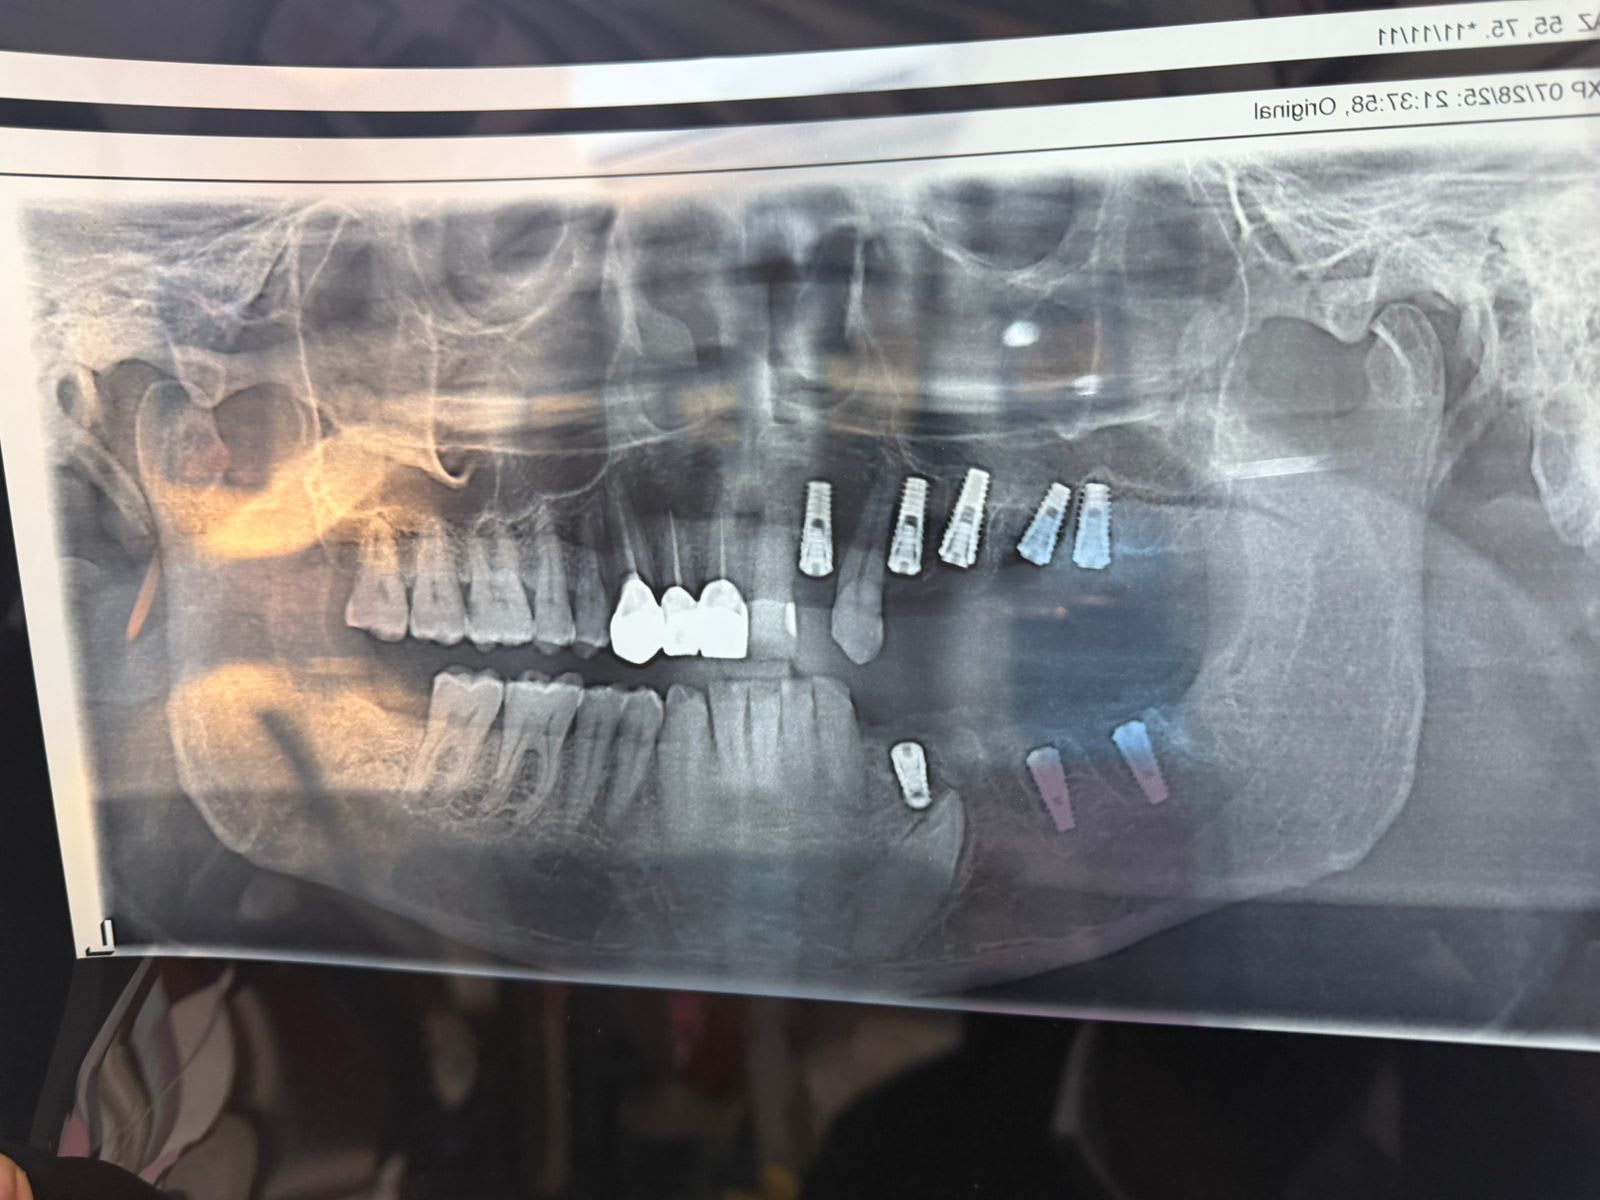

Full mouth rehabilitation with dental implants for complete functional and cosmetic restoration.

Full mouth rehabilitation with dental implants for complete functional and cosmetic restoration.